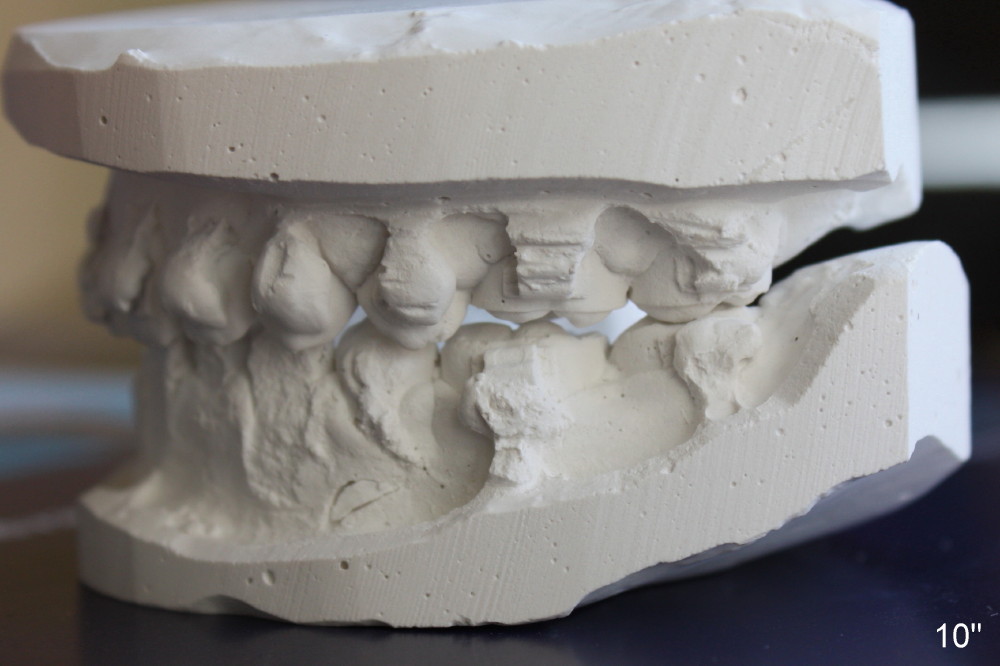

A 13-year-old Asian girl seeks orthodontic treatment for crowding. The lower 2nd bicuspids are congenitally missing (Fig.1,8), whereas the upper right one rotates 180° and the upper left is partially impacted (Fig. 1, 7). The lip muscles strain when the lips close (Fig.3). Orthodontic treatment started with extraction of four affected teeth (#4,13, K and T) 6 months ago. .018' niti wires are being used. Dental midlines do not coincide preop and intraop (Fig.4,4'). Pre-op front view shows that the upper dental midline coincides with the facial one (Fig.1'). There is Class I canine and molar relationship on the right (Fig.5,5',9,9'); open bite on the left (Fig.6,6',10,10').

Update: The left open bite was closed less than one month by wearing elastics between upper and lower teeth (Fig. 6'''). The occlusal plane and midline improve (Fig.4''). Wires have gradually changed to .016x.016, .016x.022 and now .018x.025 with power chains. All the spaces are closed except the one in LR (Fig.7''-10''). What I cannot accomplish is to fix meisal (Fig.5'' (white line), 9'') and lingual (Fig.8'' arrows) inclination of LR molars, although elastic is instructed to be placed between UR7 buccal and LR7 lingual. The rectangular wires could be twisted to fix lingual inclination. Which should be done first: LR space or LR molar inclination? Click each figure for magnification.